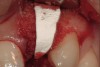

Figure 3  Surgical flap elevation reveals a 10-mm facial bony dehiscence.

Figure 3

Figure 4   Extraction socket and ridge defect augmented with particulate freeze-dried bone allograft (FDBA) saturated with rhPDGF.

Figure 4